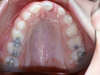

Les radios après le traitement

Vues après le traitement